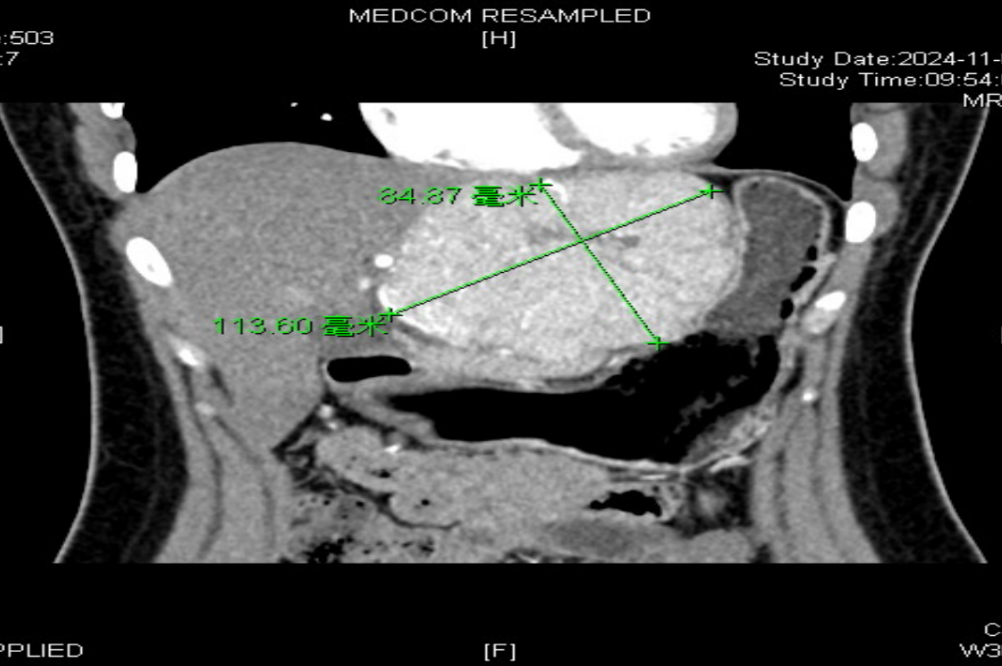

体检后发现左肝

居然长出了一个“大疙瘩”

直径约11cm

确诊为肝局灶性结节性增生